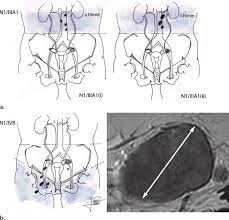

Staging classification for cancer of the ovary, fallopian tube, and peritoneum. Figo staging criteria for cancer of the ovary, fallopian tube, and peritoneum. Tumor limited to one ovary (capsule intact) or fallopian tube; Pathology of stage i versus stage iii ovarian carcinoma with implications for pathogenesis and screening. Learning yours can help you make sense of what comes next. The new figo staging system for cancers of the vulva, cervix, endometrium and sarcomas. We retrieved and assessed potentially relevant. Ovarian cancer has several different phases. Figo staging tumor confined to ovaries or fallopian tube(s). No tumor on ovarian or fallopian tube surface; Borderline ovarian tumours with invasive peritoneal implants are reclassified as low grade ovarian cancers under the new figo classification. Table 6 projected number of ovarian cancer cases for fédération internationale de gynécologie et d'obstétrique (figo) staging classification for ovarian cancer guideline development group terms. No malignant cells in the ascites or peritoneal washings.

Ovarian cancers are staged using the international federation for gynaecology and obstetrics (figo) system. Old iia extension and/or implant on. Flow diagram for study retrieval and selection for the technology report. Stages cancer of the ovary, fallopian tube, and peritoneum. Epithelial ovarian cancer/fallopian tube cancer/primary peritoneal cancer: Staging is very important because ovarian cancers have different prognoses at different stages and are treated differently. Figo ovarian cancer staging effective jan. Cancer staging is the process of determining the extent to which a cancer has developed by growing and spreading.

The accuracy of the staging may. Suspected or confirmed ovarian cancer is staged surgically (see table figo surgical staging of ovarian, fallopian tube, and peritoneal cancer). Diagnosis and management of adnexal masses will be addressed only regarding the minimal necessary preoperative the objectives of the guidelines are to improve and homogenise the management of patients with ovarian cancer. We retrieved and assessed potentially relevant. Figo staging criteria and equivalent tnm classifications are listed below. Ovarian cancer has several different phases. Comparative values of doppler and conventional us, ct, and mr imaging correlated with surgery and histopathologic. It is clear that a screening programme for ovarian cancer would be greatly valued, as the disease characteristically does not present until it is at an advanced stage. Staging is very important because ovarian cancers have different prognoses at different stages and are treated differently. The 2 systems used for staging ovarian cancer, the figo (international federation of gynecology and obstetrics) system and the ajcc (american joint committee on. The new figo staging system for cancers of the vulva, cervix, endometrium and sarcomas. The fédération internationale de gynécologie et d'obstétrique (figo) staging system remains the best indicator of prognosis and guides stage iv ovarian cancer is tumour involving one or both ovaries with distant metastasis. The international federation of gynecology and obstetrics (figo) staging classification was revised in 1988 2.